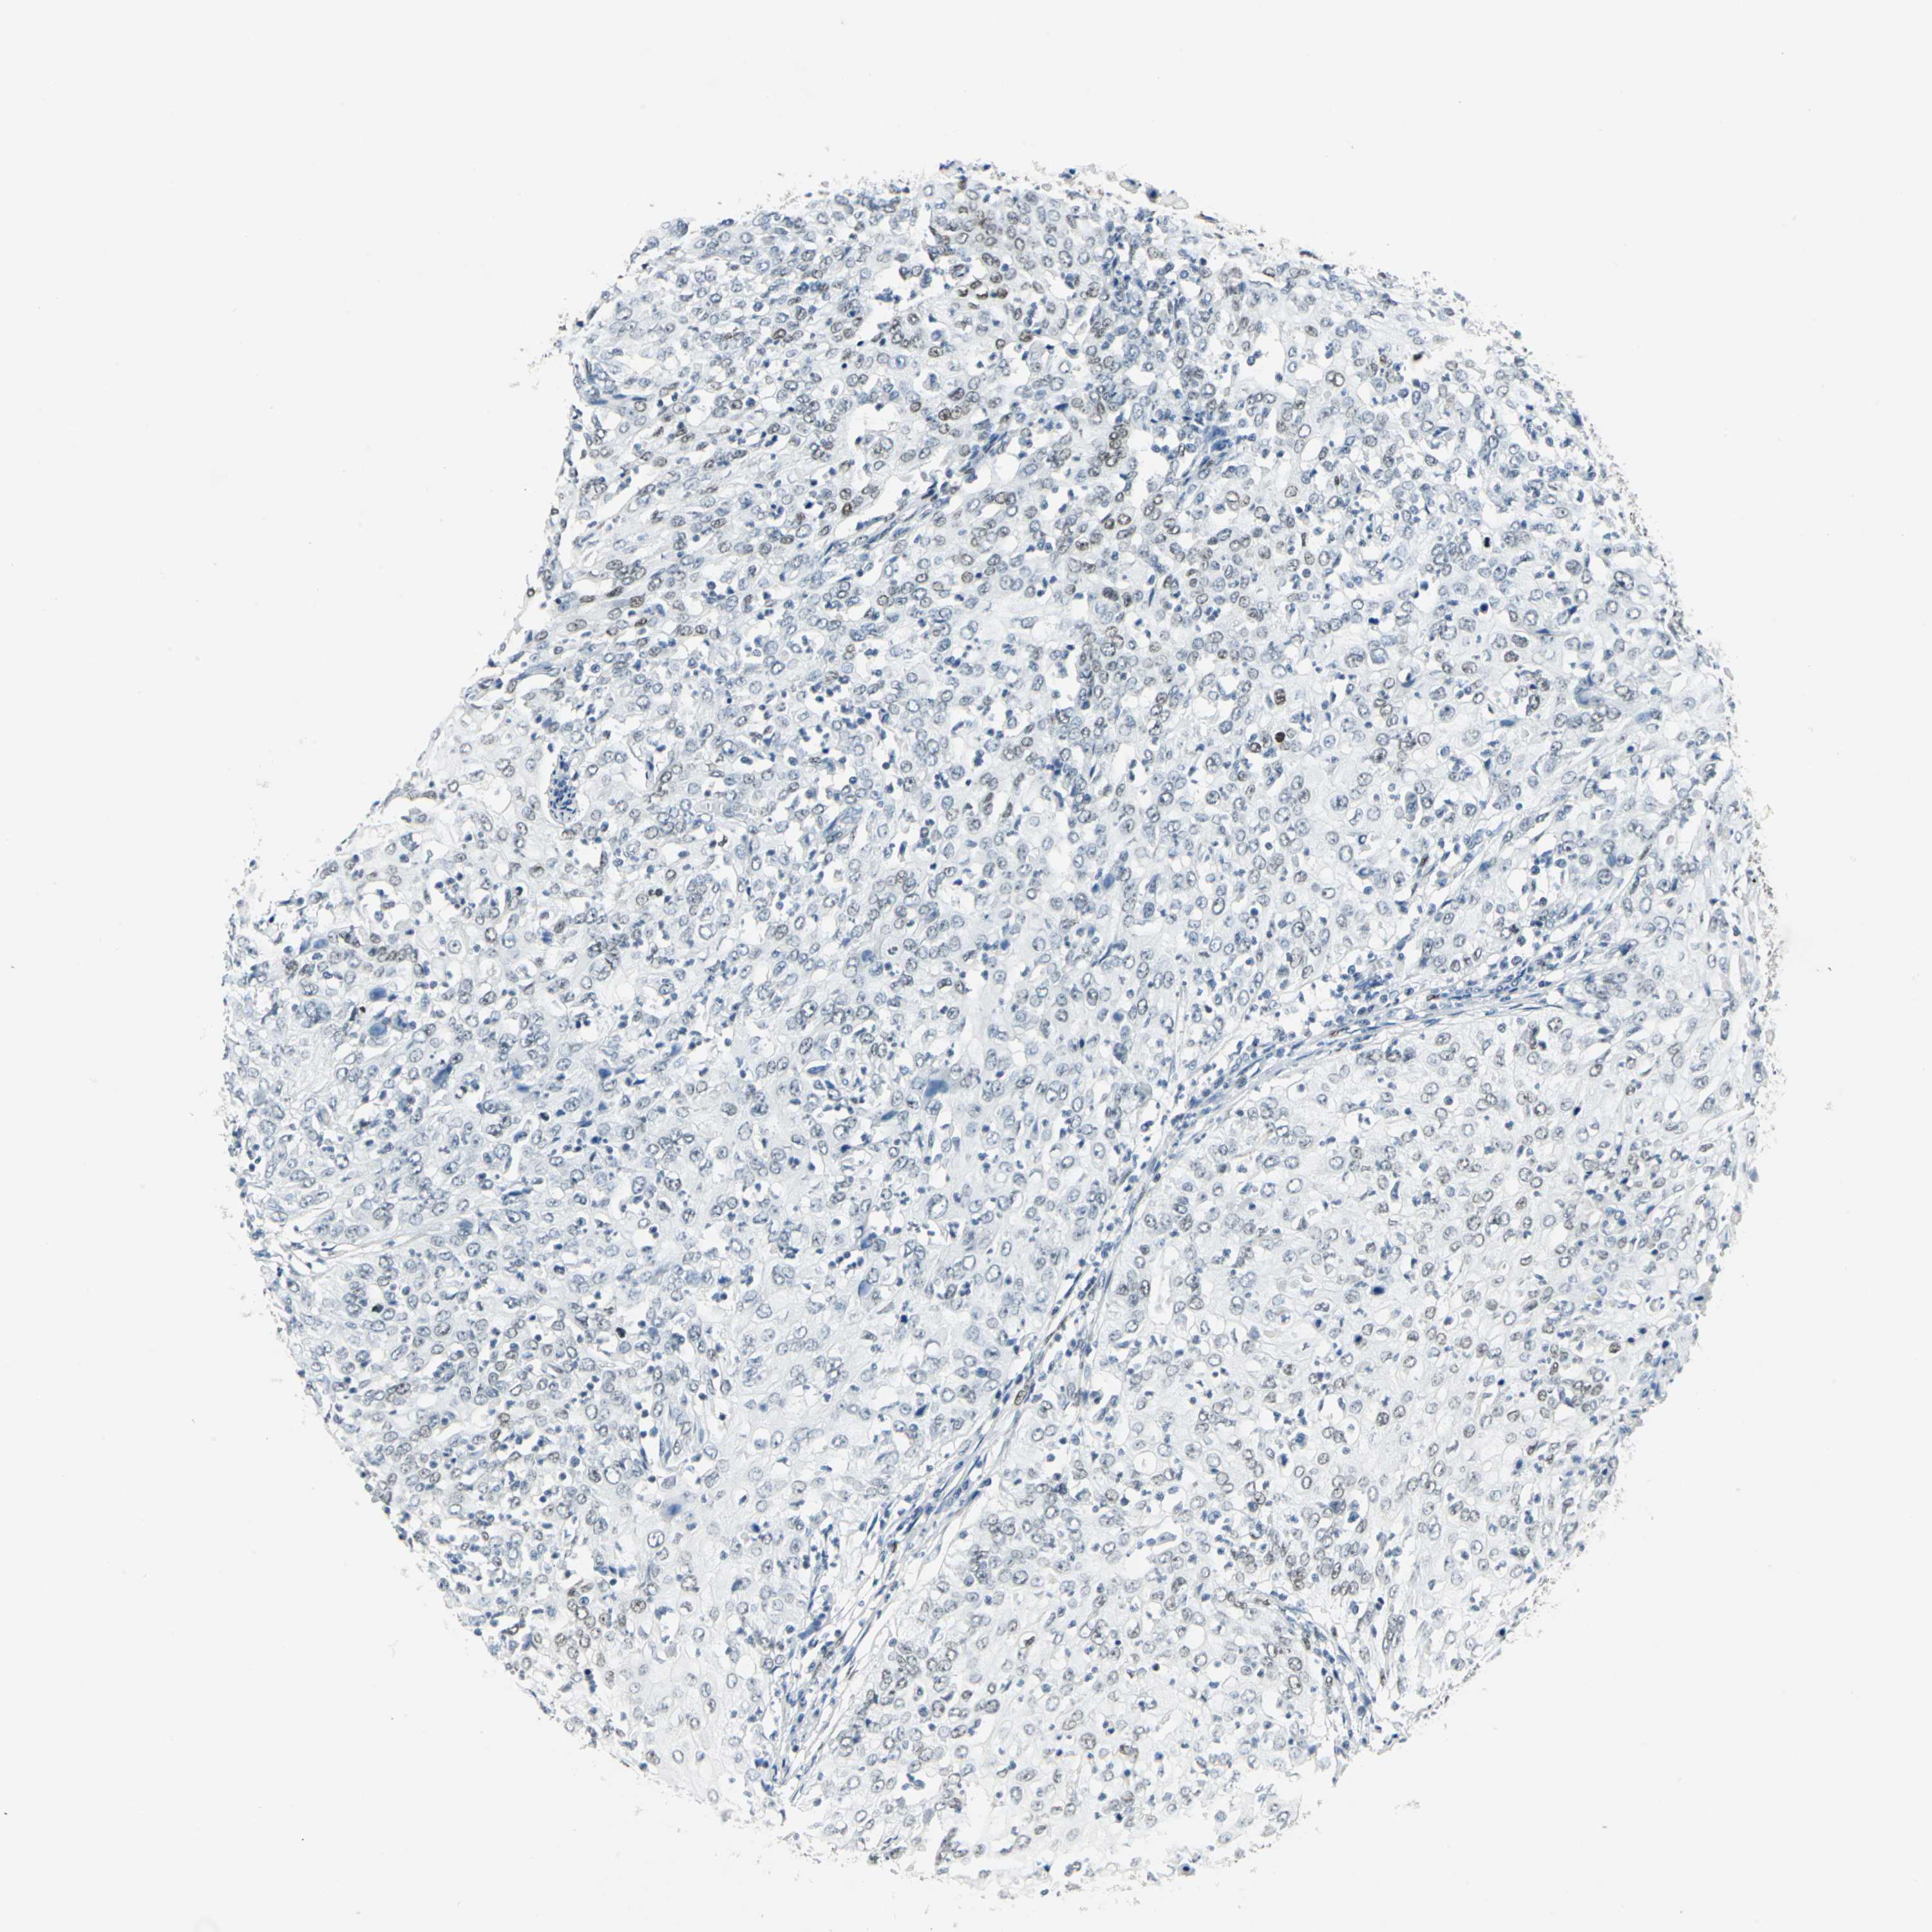

CERVICAL CANCER - Protein expressioni

A mouse-over function shows sample information and annotation data. Click on an image to view it in a full screen mode. Samples can be filtered based on level of antibody staining by selecting one or several of the following categories: high, medium, low and not detected. The assay and annotation is described here.

Note that samples used for immunohistochemistry by the Human Protein Atlas do not correspond to samples in the TCGA dataset.

Antibody stainingi

Antibody staining in the annotated cell types in the current human tissue is reported as not detected, low, medium, or high, based on conventional immunohistochemistry profiling in selected tissues. This score is based on the combination of the staining intensity and fraction of stained cells.

Each image is clickable and will lead to virtual microscopy that enables deeper exploration of all samples and also displays staining intensity scores, fraction scores and subcellular localization as well as patient and tissue information for each sample.

Antibody HPA003256

Antibody CAB004999

Staining

High

Medium

Low

Not detected

Intensity

Strong

Moderate

Weak

Negative

Quantity

>75%

75%-25%

<25%

None

Location

Nuclear

Cytoplasmic/membranous

Cytoplasmic/membranous,nuclear

Squamous cell carcinoma, NOS

Adenocarcinoma, NOS